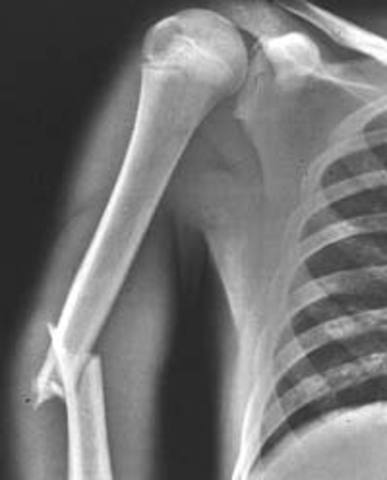

• Broken arm

Broken arm

I broke my arm when i was in !st grade in a karate accident.

I was having a test and i got to the balance part and i was doing so good by my foot slipped but i saved my fall with my arm but then i heard a crack and my elbow broke.